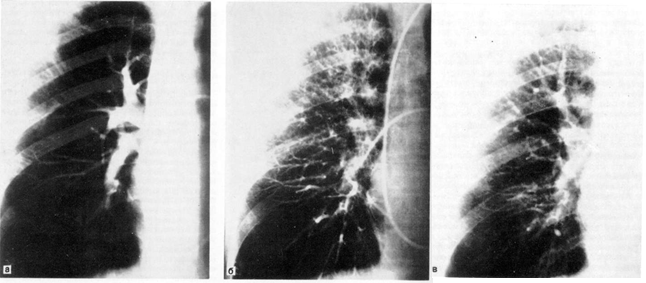

Рис. 3. Рак верхней доли левого легкого.

а — прямая рентгенограмма: б — боковая рентгенограмма.